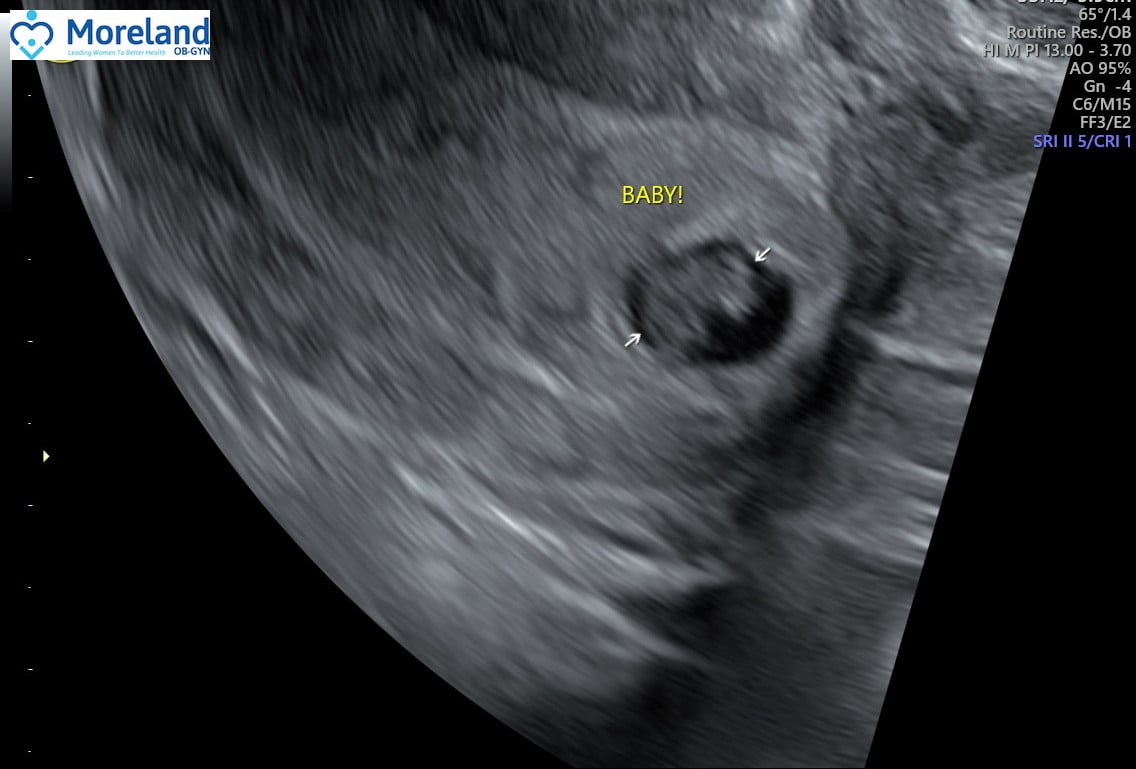

Fertility Treatments with risk of ectopic so I got my ultrasound early. Ended up being 6 weeks, 2 days and able to see the heartbeat at 115. Normal for the gestation since babes heart literally started beating 24-48 hours prior. Due Date August 6th!